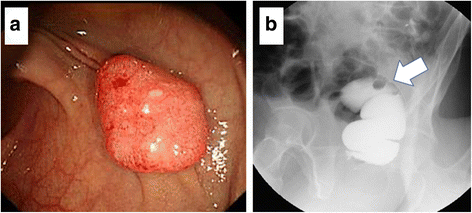

A 56-year-old man was referred to our hospital for the treatment of rectal cancer. The patient was otherwise healthy, without significant previous or current medical problems. His serum carcinoembryonic antigen (CEA) and carbohydrate antigen 19-9 levels were 1.8 ng/mL (normal, <3.4 ng/mL) and 7.7 U/mL (normal, <37 U/mL), respectively. Colonoscopy revealed a pedunculated-type tumor measuring 1.5 cm × 1.0 cm in the upper rectum, 12 cm from the anal verge, and proctographic examination revealed a filling defect in the upper rectum (Fig. 1a, b). Contrast-enhanced computed tomography (CT) revealed no swollen lymph nodes or distant metastases. We diagnosed the rectal cancer as T1N0M0 stage I and performed a laparoscopic low anterior resection. Regarding the extent of lymph node dissection, a division of the superior rectal artery root was performed without LLN dissection. A histological examination revealed a moderately differentiated adenocarcinoma that had invaded the submucosal layer (T1); the invasion depth was classified as a head invasion, without vessel or lymph duct invasion (Fig. 2a–c). Tumor budding was classified as grade 1. A total of six lymph nodes were harvested, and no lymph node metastases were detected. The postoperative course was uneventful.